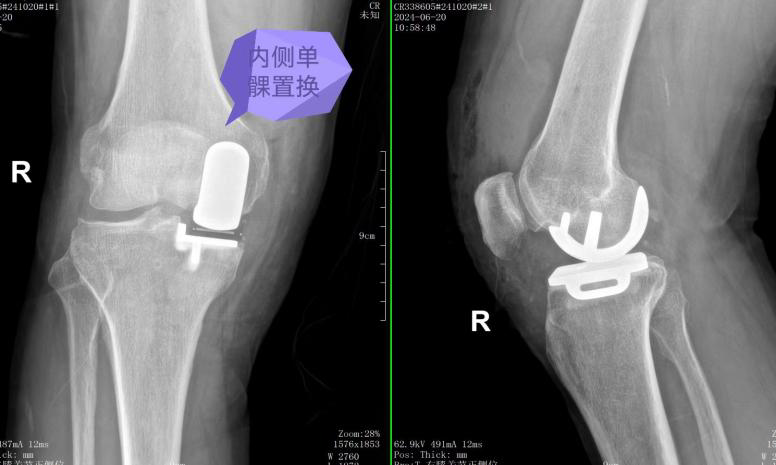

近日,pilipili 骨科顺利完成了首例膝关节单髁置换手术。此手术有效地缓解了患者因膝关节骨性关节炎所带来的疼痛,取得了显著的疗效。这一成就标志着pilipili 在推进关节保膝微创化治疗领域的发展进程中,又登上了一个新的台阶。

59岁的男性患者,近3年来因膝关节疼痛,平时不敢过多行走,日常生活受到严重影响。此前在其他医疗机构就诊时,医生普遍建议患者接受全膝关节置换手术,但由于各种原因,患者一直未能接受手术治疗。近一个月来,患者疼痛加剧,甚至无法行走,于是来到pilipili 骨科门诊寻求帮助。骨科全华山主任对患者进行了全面评估,包括详细的体检以及对其X光片和MRI影像的深入分析。全华山主任建议,患者目前不必急于进行全膝关节置换,而是可以选择一种更为保守的手术治疗方法——膝关节单髁置换。这种手术方法具有微创和精准的特点,无需切除膝关节的外侧间室及交叉韧带,只需置换内侧间室,因此术后恢复速度较快。患者入院后,骨科关节团队进行了深入的讨论,并制定了手术方案。手术在全华山主任主刀下顺利完成,整个过程持续了1小时。术后第二天,患者已能够下地并开始负重行走,活动能力得到了显著恢复。目前,患者的手术伤口已经拆线,整体恢复情况理想。

全华山主任介绍称,膝关节单髁置换术是一种维持、精准的手术技术,为目前较为理想的保膝方法。该技术适用于治疗仅涉及膝关节单间室的骨关节炎患者,通过单纯置换病变侧的软骨,同时保留所有的韧带组织。通过这种手术,患者可以快速恢复膝关节功能,从而恢复正常的生活和工作能力。与传统的全膝关节置换术相比,单髁置换术的术后恢复时间更短,其优势在于不影响膝关节其他间室的正常功能,能够最大限度地保留本体感觉和关节功能。此外,该手术具有创伤小、疗效快、恢复快、住院时间短和患者满意度较高等特点。然而,相较于全膝关节置换手术,膝关节单髁置换术对手术技术的要求更高,需要更为精准地操作。